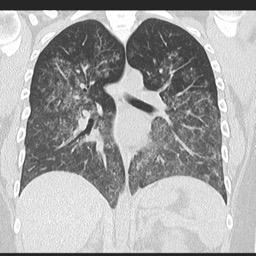

o HRCT: дифузні матові затінення та альвеолярна консолідація.

Дифузна альвеолярна кровотеча внаслідок васкуліту

Джерело: radiopaedia.org